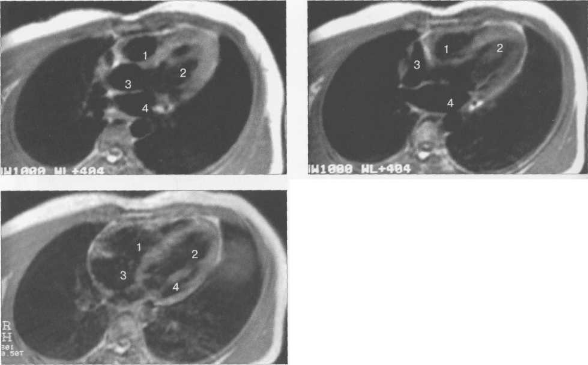

КТ АНАТОМИЯ СЕРДЦА

КТ-исследование позволяет получать поперечные (аксиальные) сечения сердца. Стандартная пошаговая КТ и даже спиральная КТ не получили распространения для исследования морфологии и функции сердца. Более тщательный анализ внутрисердечных структур возможен с помощью многослойной спиральной КТ (МСКТ) в условиях внутривенного контрастирования. КТ-изображения сердца и сосудов на различных уровнях представлены на рис. 9.34.

Рис. 9.34. КТ сердца и сосудов.

1 — правый желудочек; 2 — левый желудочек; 3 — правое предсердие; 4 — левое предсердие; 5 — межжелудочковая перегородка; 6 — межпредсердная перегородка; 7 — верхняя полая вена; 8 — восходящая часть аорты; 9 — нисходящая часть аорты; 10 — легочный ствол; 11 — правая легочная артерия; 12 — диафрагма; 13 — легочные вены.